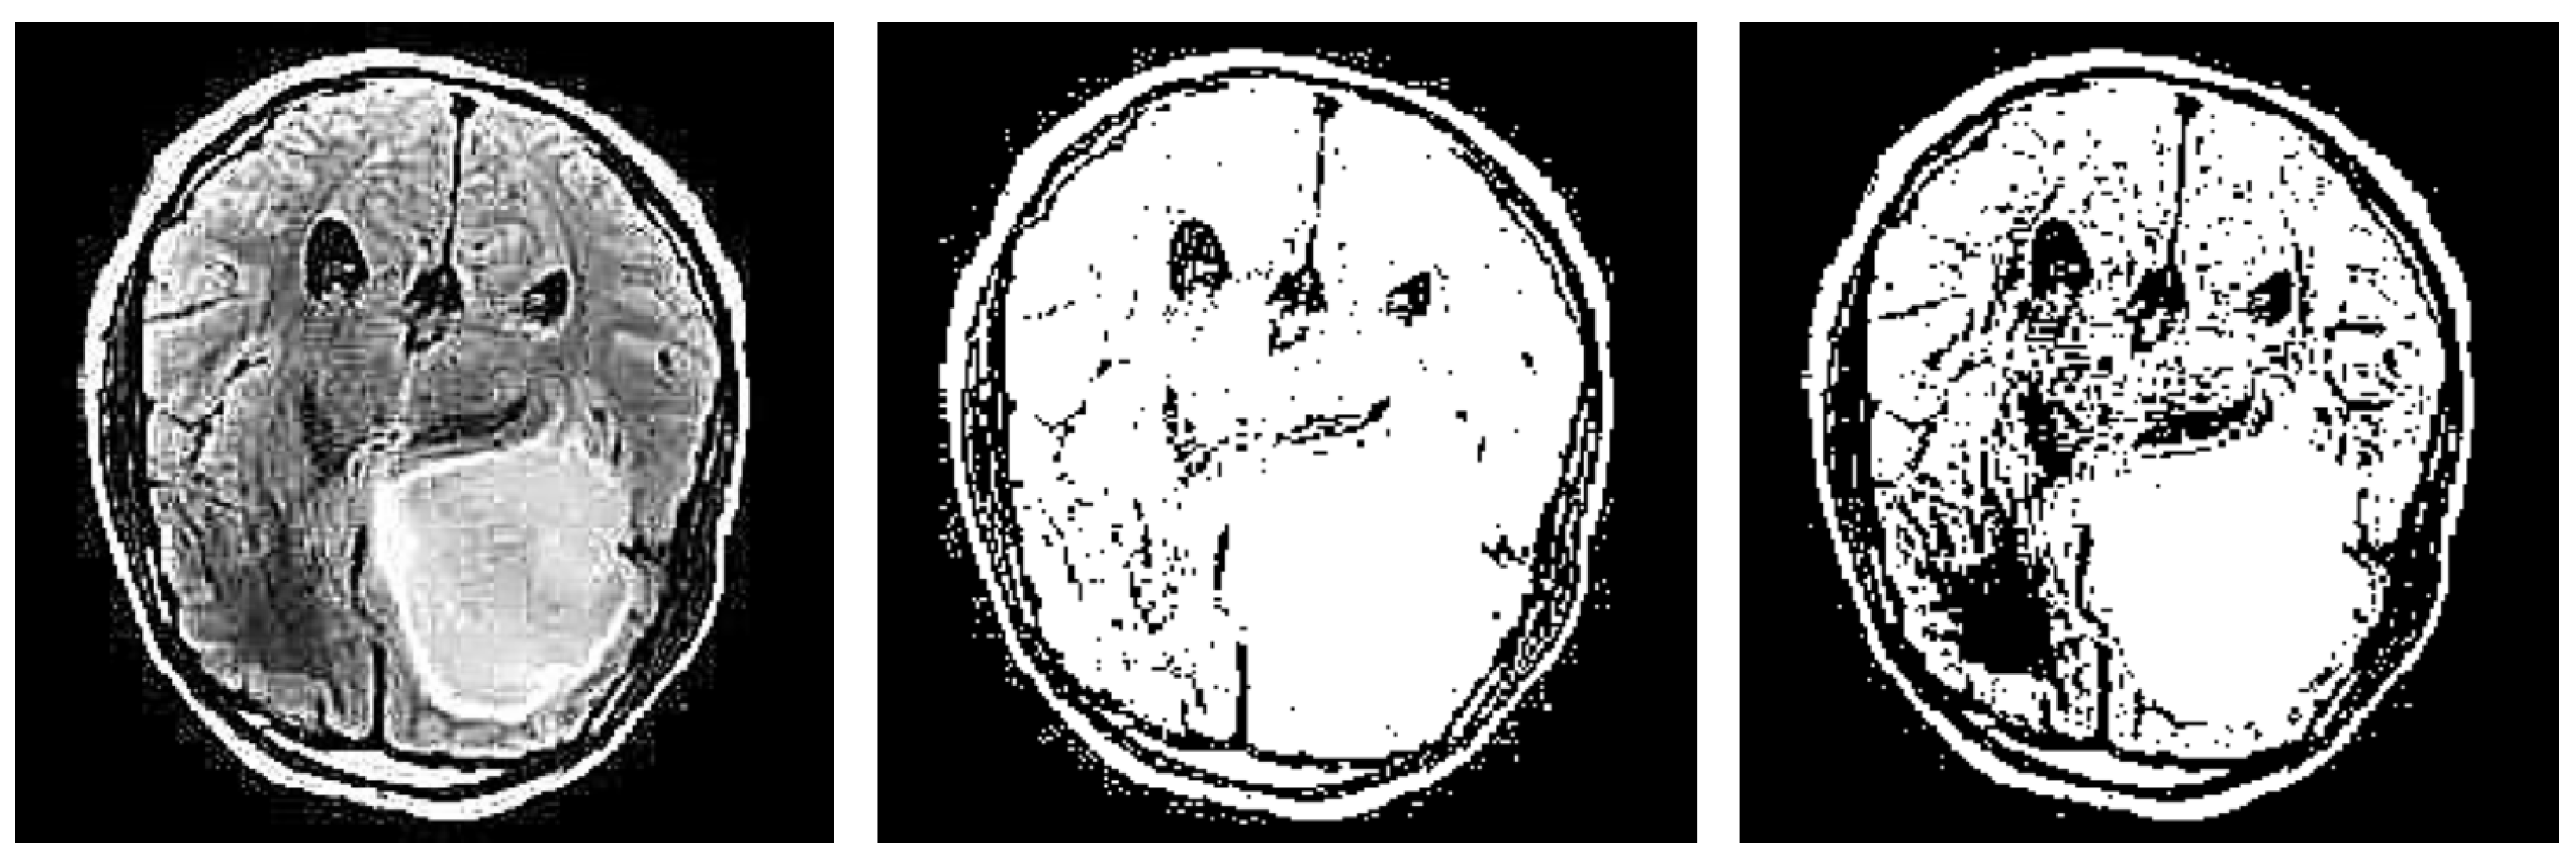

Another notable drawback observed in the proposed refinement mechanism is the potential inconsistency in creating the brain mask (see examples in Figure 19). The method relies on the edges detected by the different techniques and subsequently extracting the largest contour as the brain mask. However, in some instances, this process may yield inconsistent results.

One issue arises when the detected edges fail to accurately define the boundaries of the brain, resulting in incomplete or fragmented contours. Consequently, the extracted brain mask may cover only a portion of the actual brain region or extend beyond its boundaries, leading to false interpretations during explanation generation.

Figure 19. Instances of wrong brain mask production.

Jimaging 10 00232 g019